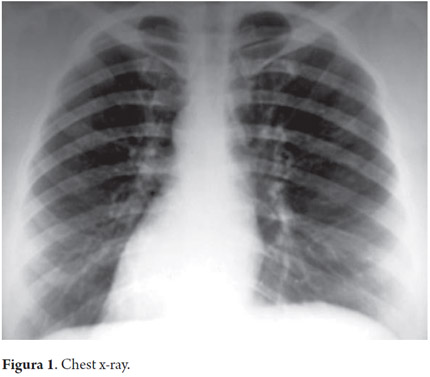

Given that clinical and paraclinical examinations indicated extrahepatic cholestasis, it was decided to perform ERCP. A posteroanterior chest x-ray during preoperative cardiovascular assessment showed dextrocardia (Figure 1).